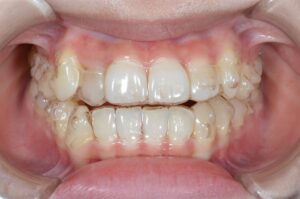

①写真撮影

今の歯並びを色々な角度から撮影します。

せっかくなので矯正前→現在(No.40)で並べてみます。